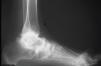

Las principales pruebas complementarias de diagnóstico son las proyecciones radiográficas en carga, donde se demuestra una disminución del ángulo de Moreau-Costa-Bartani (fig. 5) y del ángulo de divergencia astragalocalcáneo. La radiografía de perfil permite además observar la zona de inflexión del arco plantar (fig. 5). Según la huella plantar, clasificamos este pie en precavo o cavo de primer o segundo grados (fig. 6). El precavo, o cavo dinámico, es la situación observable en el niño con una desnivelación reductible y una huella plantar prácticamente normal. El cavo de primer grado es secundario a una desnivelación parcialmente fijada, con reducción de la banda externa de la huella (inferior a un tercio de la amplitud del antepié), mientras que en el cavo de segundo grado, al ser la desnivelación más importante, se marca tan sólo la huella de los pilares anterior y posterior.

Figura 5. Pie cavo anterior: retropié normal, antepié verticalizado (A), y pie cavo posterior: retropié muy verticalizado (B). Ángulo de Moreau-Costa-Bartani reducido.